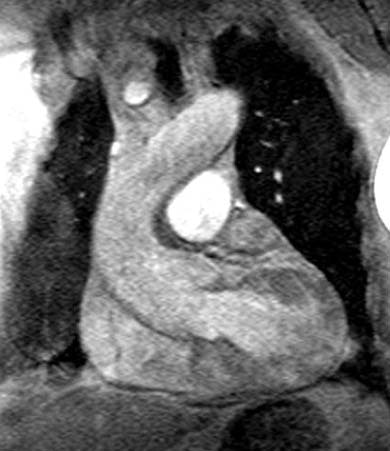

Marfan's Syndrome:

In the images below, the arrows point to the dilated aortic root which has a characteristic "onion bulb" or "pear" shape. The sinotubular junction is effaced, and there is mild aneurysmal enlargement of the sinuses of Valsalva (measuring 5.1 cm).